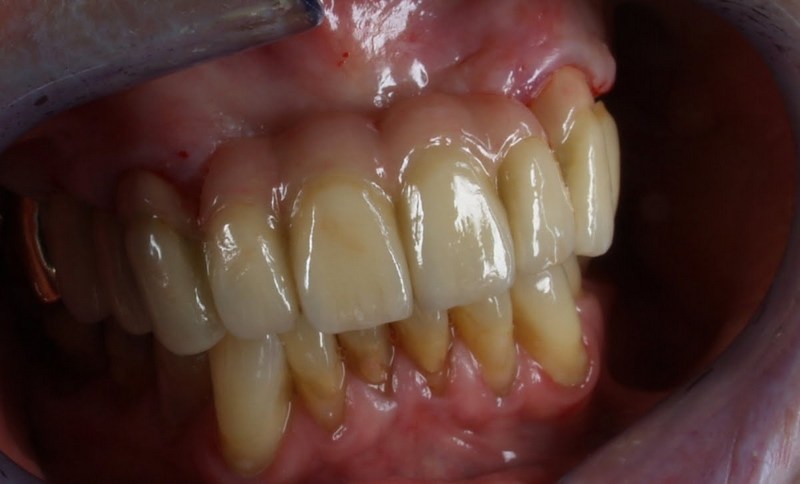

Vom Langzeitprovisorium zur TEK 1 Arbeit